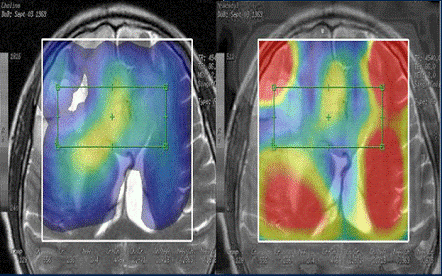

Визуализация с помощью Discovery MR750w 3.0T не похожа на то, что использовалось ранее. Посредством градиентов высокой производительности при коротком времени сканирования, неизменной четкости и однородности с использованием РЧ передатчика MultiDrive, а также большой области сканирования 50x50x50 см, Discovery MR750w предлагает бескомпромиссное покрытие и качество.

RF Transmit - посредством полностью автоматического и независимого радиочастотного контроля амплитуда импульсов и фазы, MultiDrive RF Transmit позволяет получить неизменно четкие изображения 3.0T.

Optical RF (OpTix) - большое число каналов, аналогичное цифровой-оптической передачи сигнала (где это играет значение), внутри помещения для сканирования служит для сведения к минимум шумов и деградации сигнала вдали от пацента, повышая комфорт и безопасность последнего.